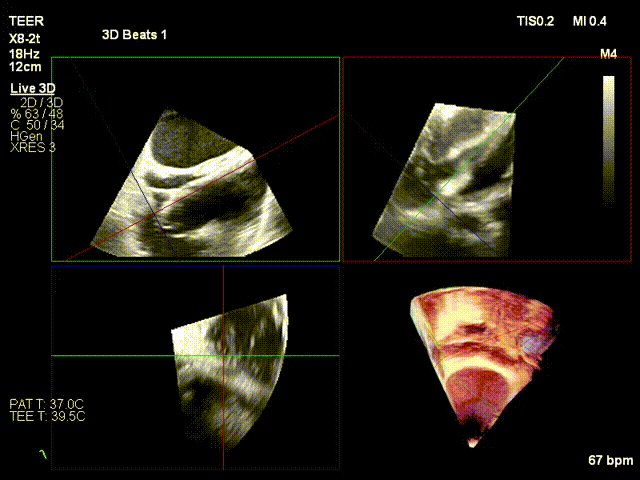

Deployment of the anchoring component under the MPR view